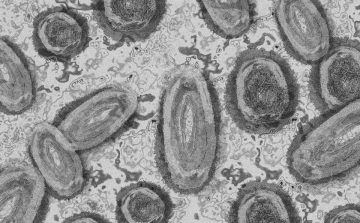

Tovább nőtt a majomhimlő-fertőzöttek száma Magyarországon

Újabb két embernél igazolt majomhimlő-fertőzést a Nemzeti Népegészségügyi Központ (NNK) a 33. héten - augusztus 15-től 21-ig -, ezzel 64-re nőtt a magyarországi esetek száma.

Egy 3 év alatti gyermek fertőződött meg majomhimlővel Belgiumban

Belgiumban egy 3 év alatti gyermek fertőződött meg majomhimlővel - számolt be róla szerdán a Sudinfo hírportál.

Megfertőződött a majomhimlővel egy gyerek Németországban

Megfertőződött majomhimlővel egy négyéves kislány Németországban - jelentették kedden német hírportálok az országos közegészségügyi intézet (RKI) adatai alapján.